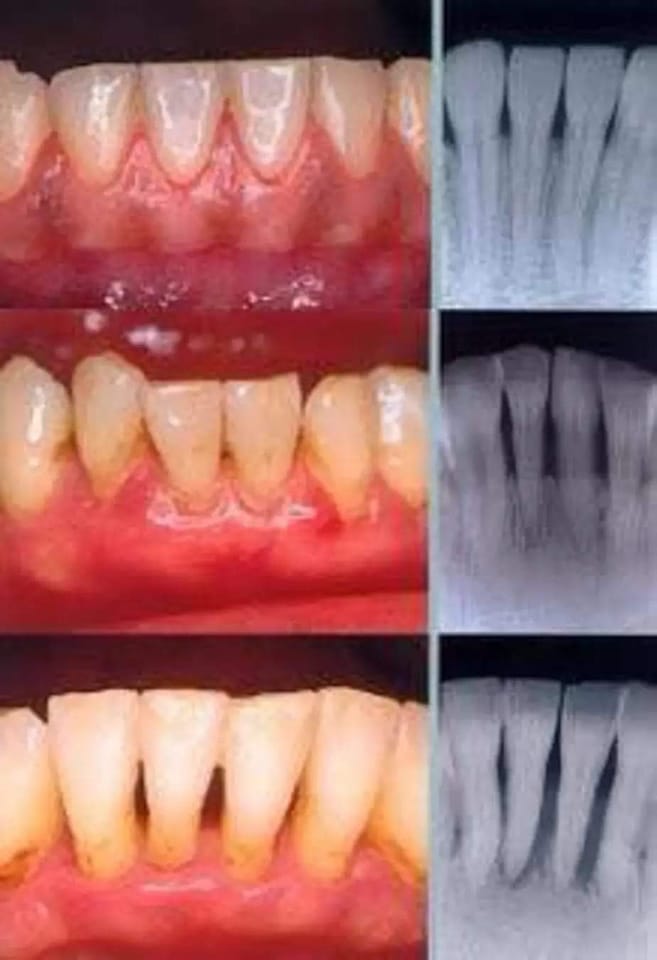

أنواع التهاب اللثة

هي مجموعة التهابات تؤثر على الأنسجة المحيطة بالأسنان، والتي تتكون من اللثة والعظم والرباط الداعم للأسنان، وتعتبر السبب الرئيسي لسقوط الأسنان، وتظهر أمراض اللثة في أي عمر، خصوصا في كبار السن، وحسب إحصائيات علمية فإن أكثر من نصف الناس يصابون بالتهاب باللثة في نحو سن العشرين، وأكثر من ثلاثة أرباع الناس يصابون بالتهاب فيها بعد عمر 35 سنة، وهذا يدل على زيادة شيوع تلك الأمراض في الكبار، وهو ناتج عن إهمال نظافة الفم، ما يؤدي إلى تراكم الجير والكلس على الأسنان.

وهناك عدة انواع لالتهابات اللثة منها:

- التهاب اللثة الحاد أو السطحي

- والتهاب اللثة المزمن

- والتهاب اللثة العنيف

علامات التهابات اللثة

وهناك العديد من العلامات التى تعرف من خلالها اصابتك بالتهابات اللثة ومن ثم المبادرة إلى العناية والعلاج ومنها:

- حدوث نزف اللثة في اثناء الغسل بالفرشاة.

- احمرار لون اللثة.

- تورم وانتفاخ اللثة نتيجة الالتهابات المصاحبة.

- تكون جيوب عميقة حول الاسنان.

- حدوث تخلخل في الاسنان وتباعدها عن بعضها البعض.

- مع تكون صديد وخراج.

- خروج صديد على اللثة.